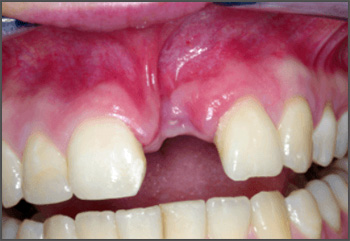

A cleft lip can range from a little notch in the coloured part of the lip to a complete separation of the upper lip which can extend up and into the nose. This can affect one side of the mouth (unilateral) or both sides (bilateral), and can be complete (meaning the cleft goes up into the nose) or incomplete.

A cleft lip can also affect the gum where the teeth come through. Again, this can range from a small notch to a complete separation of the gum into two parts.

Surgery is needed to close the gap left by the cleft. This will usually happen when the child is under a year old.

Every cleft is unique, just like every child, so the exact treatment pathway will vary. It may include further surgery to help with issues such as speech and growth of adult teeth. It may also include speech therapy, help with hearing, orthodontic work, etc.